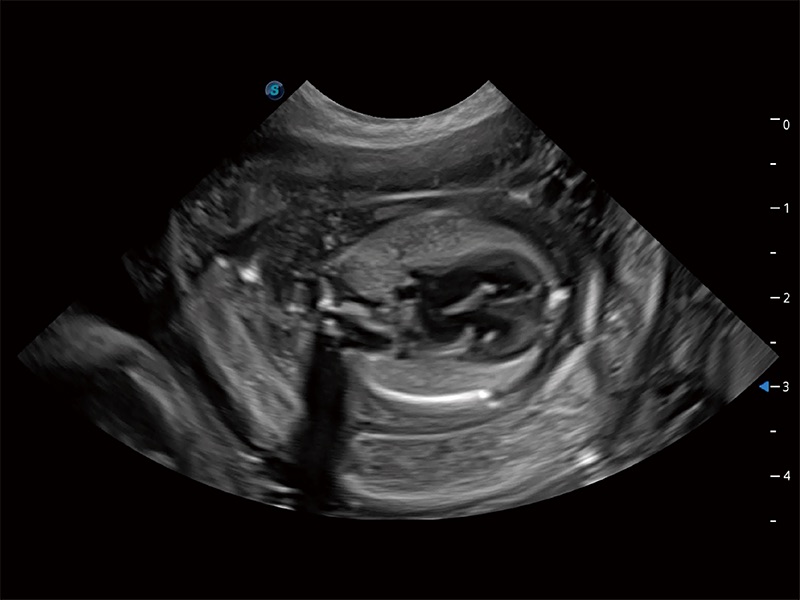

动物是人类最亲密的朋友和最值得信赖的伙伴。九州酷游也一直致力于探索动物专用的超声影像解决方案。全新推出的ProPet系列,是九州酷游在动物超声影像智能化、专业化、精准化的一次跨越式革新。动物不能用言语来表述自己的不适,通过超声影像,ProPet系列搭建了动物医生与不同物种沟通的“桥梁”,为动物医生注入了“治愈之力”。 ProPet 80 是九州酷游匠心打造的一款高端动物专用彩超,采用性能卓越的全新硬件架构,极大提升超声系统的运行效率和数据处理能力,帮助动物医生从容应对日益增多的挑战性病例和日益多样化的临床需求。

高性能和先进的临床应用工具可以为动物医生提供临床信心。ProPet 80 搭载了先进的腹部和浅表应用工具,帮助医生在日常临床实践中发挥前所未有的作用。

ProPet 80 全新的动物超声智能软件和丰富的探头群,为动物医生提供了高清晰度和精细分辨率的图像,无论在宠物、马科、畜牧还是实验室动物等应用中都可以轻松应对,为您的日常工作带来满意的体验。